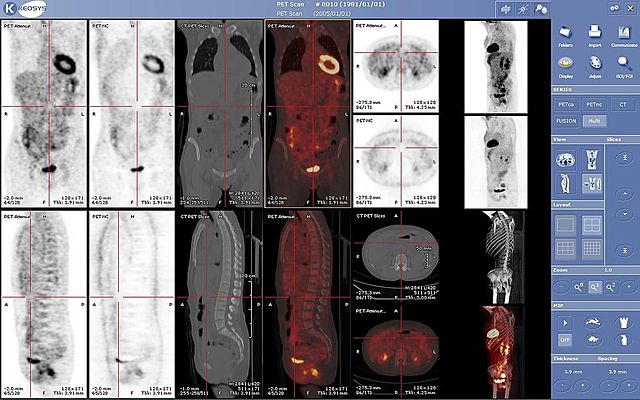

• MEDICINA NUCLEAR

MEDICINA NUCLEAR

La Medicina Nuclear en Españ a comienza en 1949 cuando el Dr.Blanco - Soler en el hospital de la cruz roja de madrid comienza a trabajar en el diagnóstico preventivo de la tiroides. .